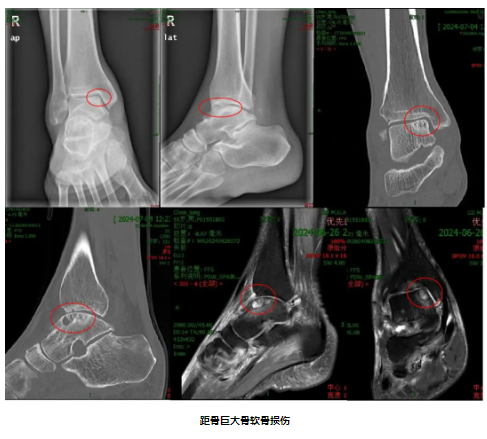

55岁的陈先生近4年来反复出现右侧踝关节肿痛,逐渐影响日常生活。其就诊过多家医院,先后尝试过多种治疗方式,总体效果并不满意,而患肢的疼痛症状和活动功能障碍也越来越糟糕。后来陈先生了解到广东医科大学附属医院运动医学科钟环副主任(主持工作)团队在足踝疾病诊疗方面具有丰富的经验,遂到附属医院就诊。经过运动医学团队钟环主任医师和黄华军博士后的询问病史和详细查体后,诊断为右侧距骨骨软骨损伤(Hepple Ⅴ期),目前的距骨已出现了不可逆的骨软骨损伤,必须对关节软骨面进行手术修复重建。入院后的踝关节CT以及MRI显示距骨骨软骨损伤病灶面积较大且位置深,分布于距骨内侧穹隆中后方,且出现直径、深度均大于1cm骨囊性变。专科团队经过反复术前病情讨论后一致认为,患者正值壮年,过早的关节融合手术将给生活质量带来较大的影响,而全踝关节置换手术则要考虑假体生存率带来的二次翻修手术问题。综合考虑患者自身年龄、身体机能以及意愿因素,团队决定采用经内踝截骨入路的自体髂骨骨膜骨移植修复距骨骨软骨损伤+距腓前韧带修补的二联手术方案。

然而,术前影像学资料显示,患者距骨病灶的位置靠近踝关节后内侧,常规的内踝纵行截骨难以获得良好的暴露及骨移植操作空间,给手术增加了较大的难度。此外,该术式要求术者对病灶形态精确评估和规划,在移植过程中因移植物和缺损病灶在曲率形态上的失匹配将导致移植术后发生中晚期的创伤性关节炎。对此,团队的欧阳汉斌博士后与黄华军博士后决定采用数字骨科技术,最终确定髂骨的最佳供区。